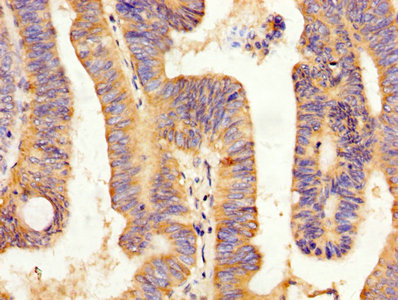

IHC image of CSB-PA12214A0Rb diluted at 1:200 and staining in paraffin-embedded human small intestine tissue performed on a Leica BondTM system. After dewaxing and hydration, antigen retrieval was mediated by high pressure in a citrate buffer (pH 6.0). Section was blocked with 10% normal goat serum 30min at RT. Then primary antibody (1% BSA) was incubated at 4°C overnight. The primary is detected by a biotinylated secondary antibody and visualized using an HRP conjugated SP system.

IHC image of CSB-PA12214A0Rb diluted at 1:200 and staining in paraffin-embedded human colon cancer performed on a Leica BondTM system. After dewaxing and hydration, antigen retrieval was mediated by high pressure in a citrate buffer (pH 6.0). Section was blocked with 10% normal goat serum 30min at RT. Then primary antibody (1% BSA) was incubated at 4°C overnight. The primary is detected by a biotinylated secondary antibody and visualized using an HRP conjugated SP system.